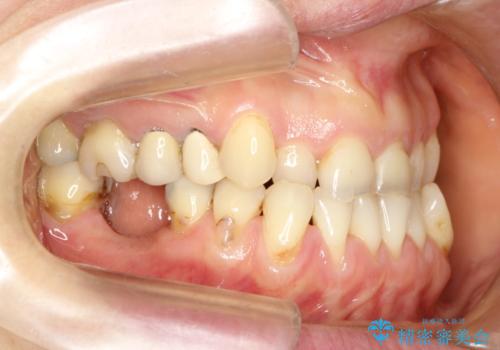

反対咬合や欠損を治療したい インビザライン矯正とオールセラミックブリッジ

- 虫歯治療がうまく進まないとのことで来院された患者様です。

虫歯治療や欠損補綴治療も必要でしたが、前歯が反対咬合であったので、セラミッククラウンやブリッジによる治療と並行して矯正治療を提案しました。

海外出張にとどまらず海外赴任もあり、途中2度の妊娠もあったため、治療には非常に長い期間を要することとなりました。